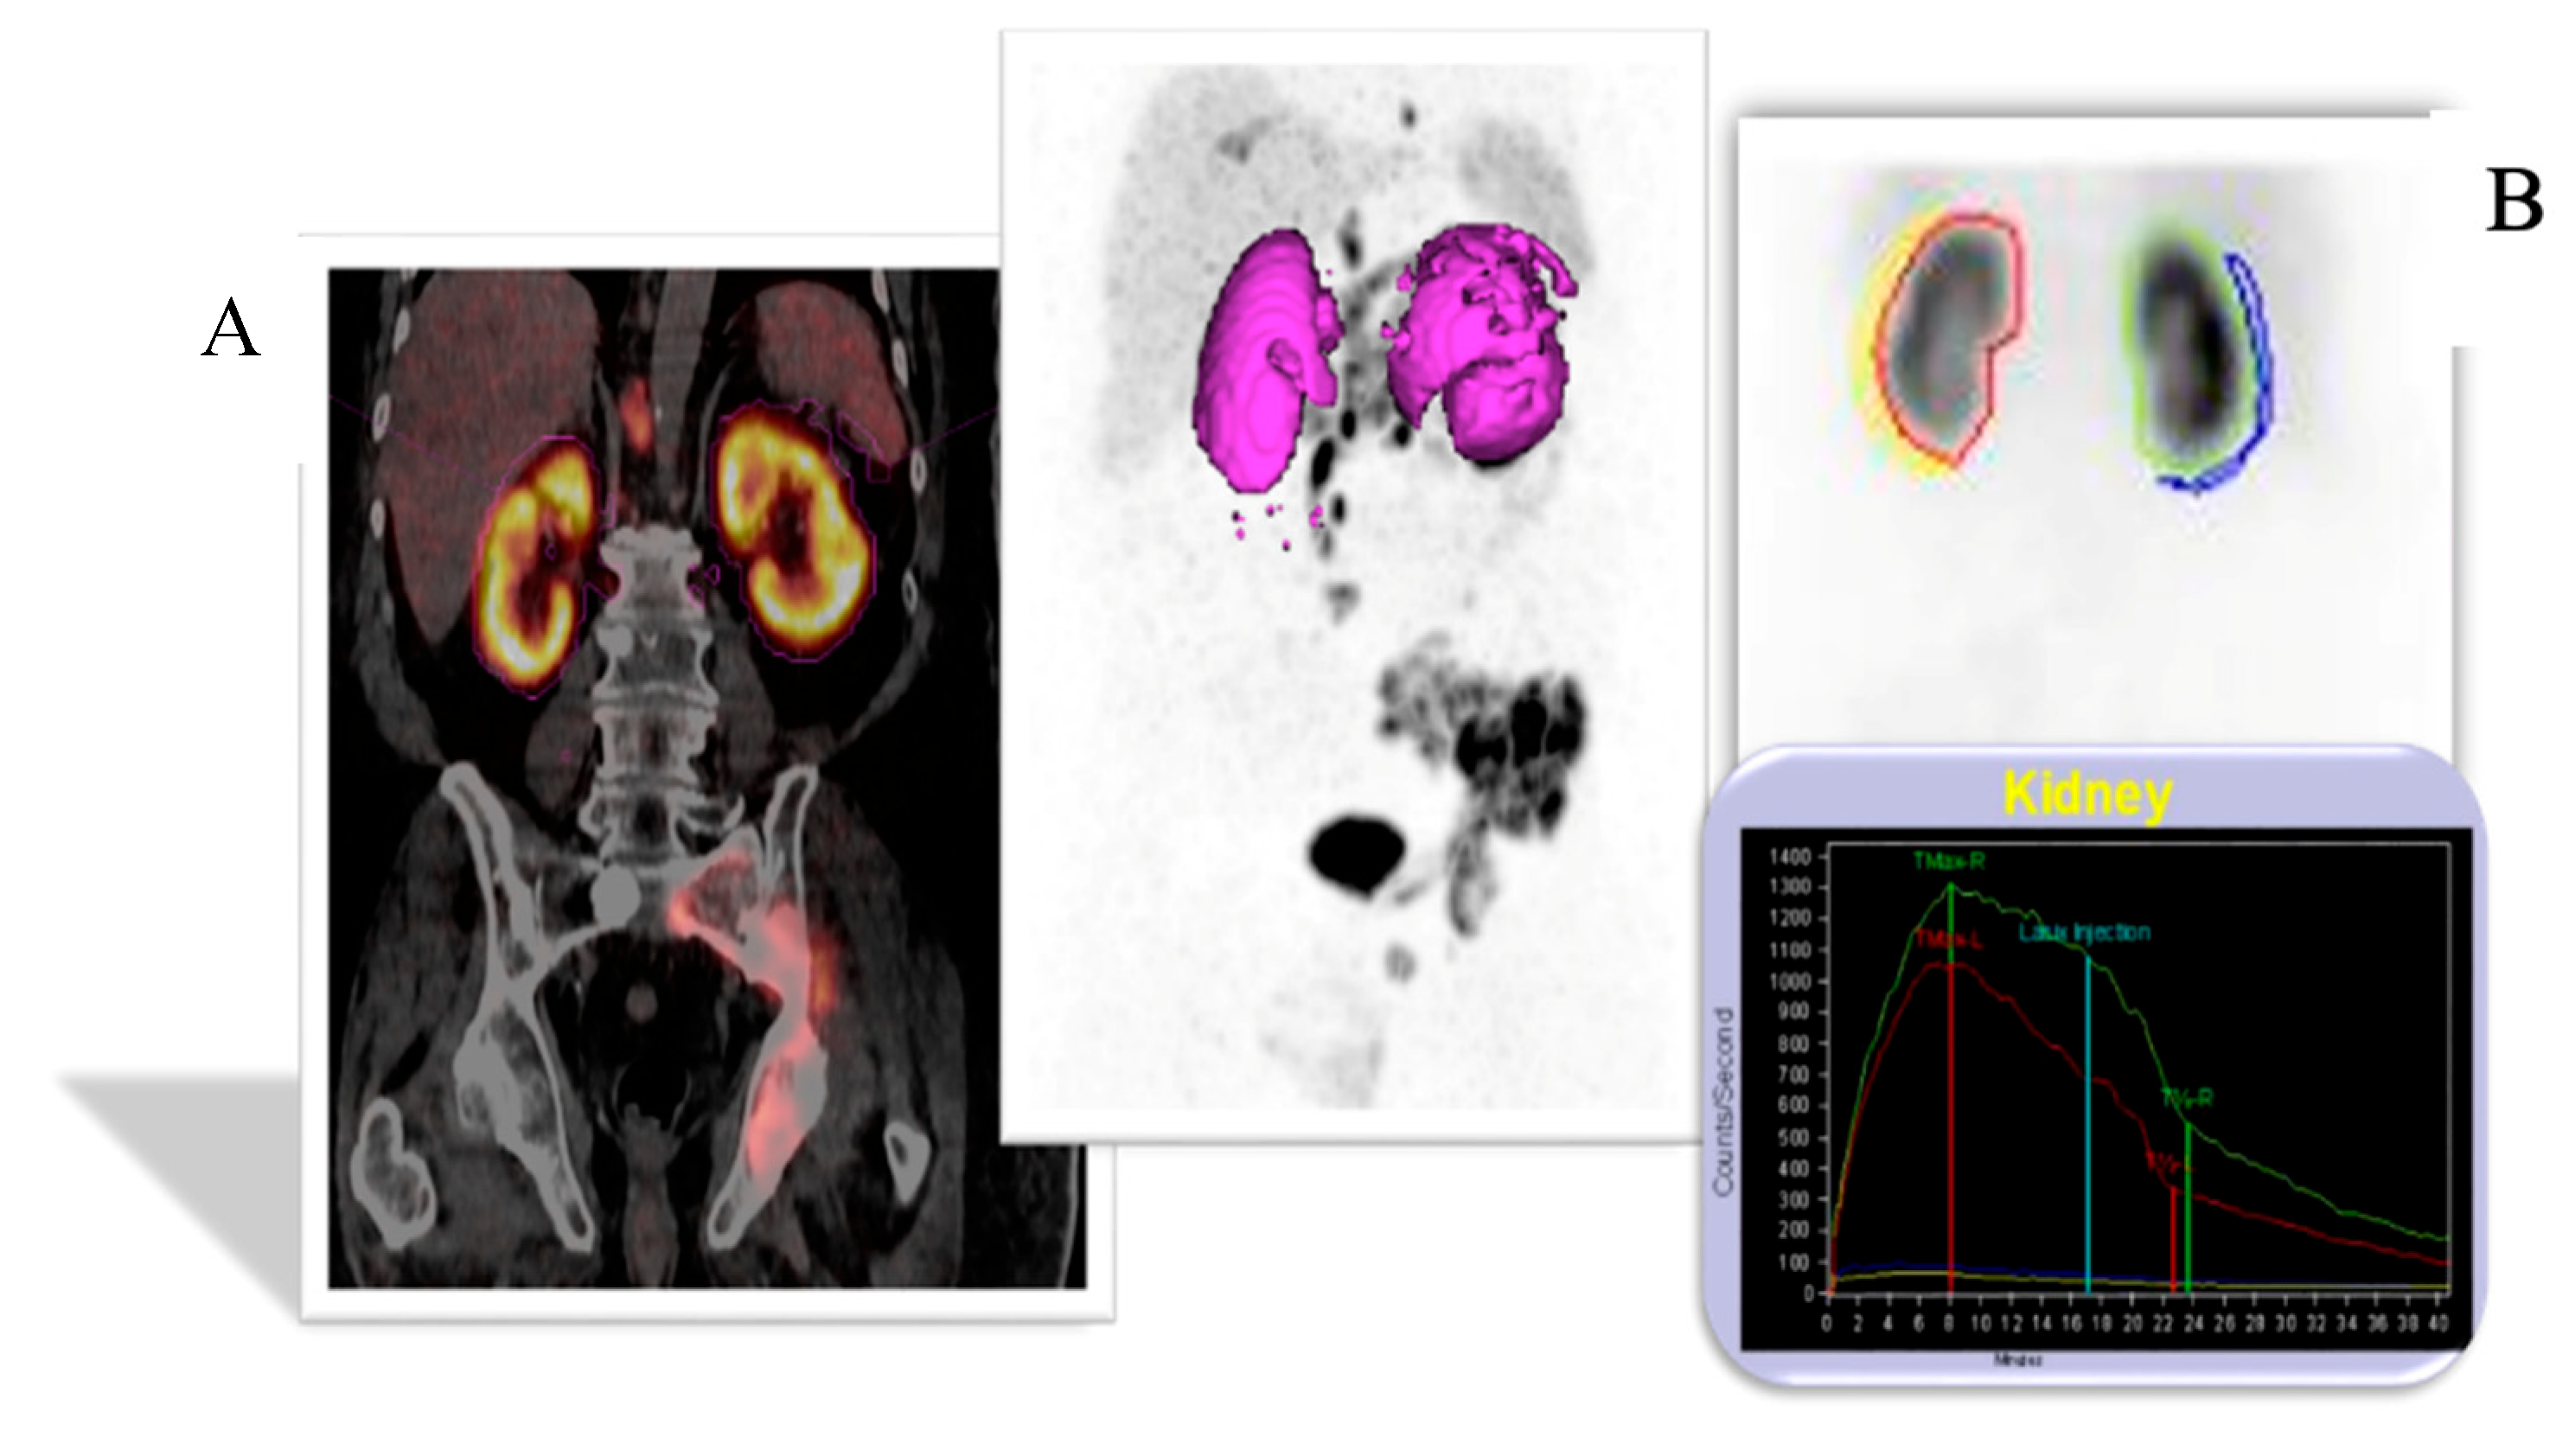

2.1.1. 68Ga-PSMA PET/CT

2.1.2. 68Ga-PSMA PET/CT Image Analysis

2.1.3. 99mTc-MAG3 Renal Scintigraphy